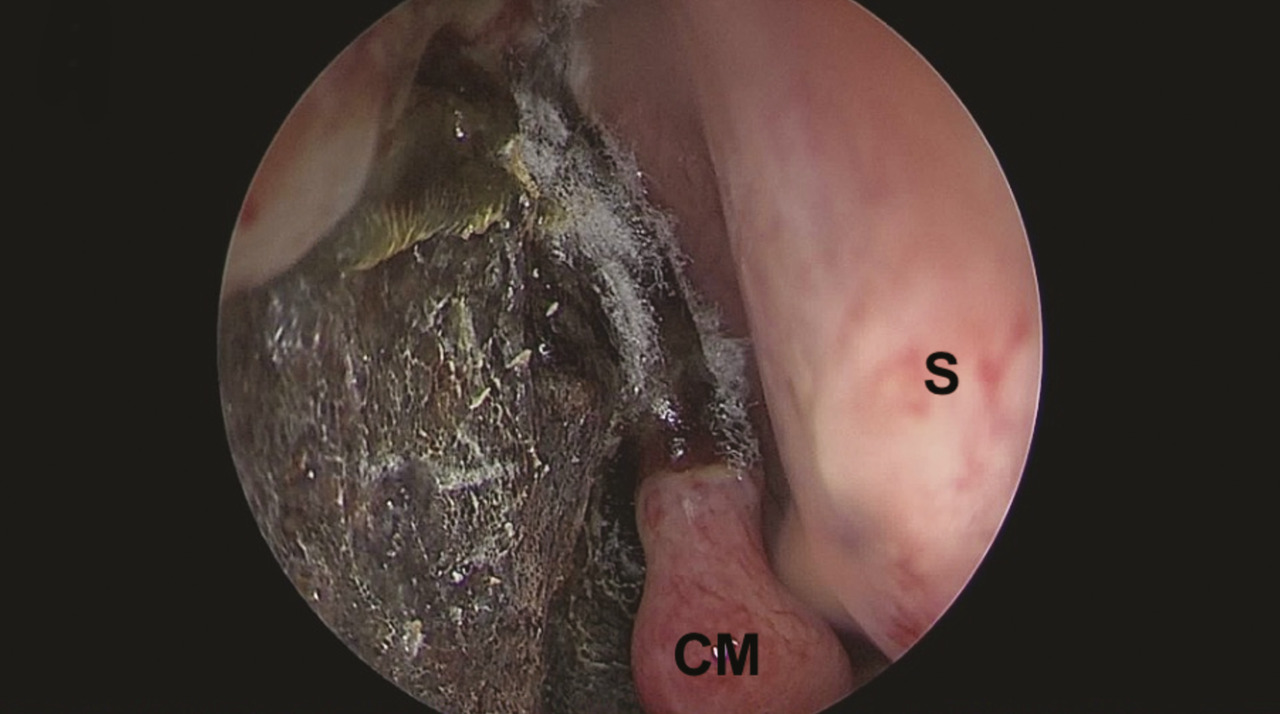

L’examen endoscopique de la fosse nasale doit être réalisé en urgence devant toute suspicion clinique. Il recherche un aspect atone, voire nécrotique, des muqueuses, typique des mucormycoses (fig. 5). Il permet de confirmer le diagnostic, par la réalisation de biopsies pour analyses mycologiques et anatomopathologiques. L’examen direct mycologique réalisé en urgence avec un microscope à fluorescence peut établir le diagnostic en identifiant les filaments mycéliens évocateurs. L’examen anatomopathologique retrouve des filaments larges, non septés, associés à un infiltrat fongique périnerveux, avec une réponse inflammatoire neutrophilique et surtout des images d’angio-invasion fongique avec thrombose et nécrose (fig. 3). La culture mycologique est négative dans plus de la moitié des cas dans une série française.4 La PCR Mucorales sur les biopsies et sur prélèvement sanguin peut être une aide au diagnostic puis dans le suivi.6,7